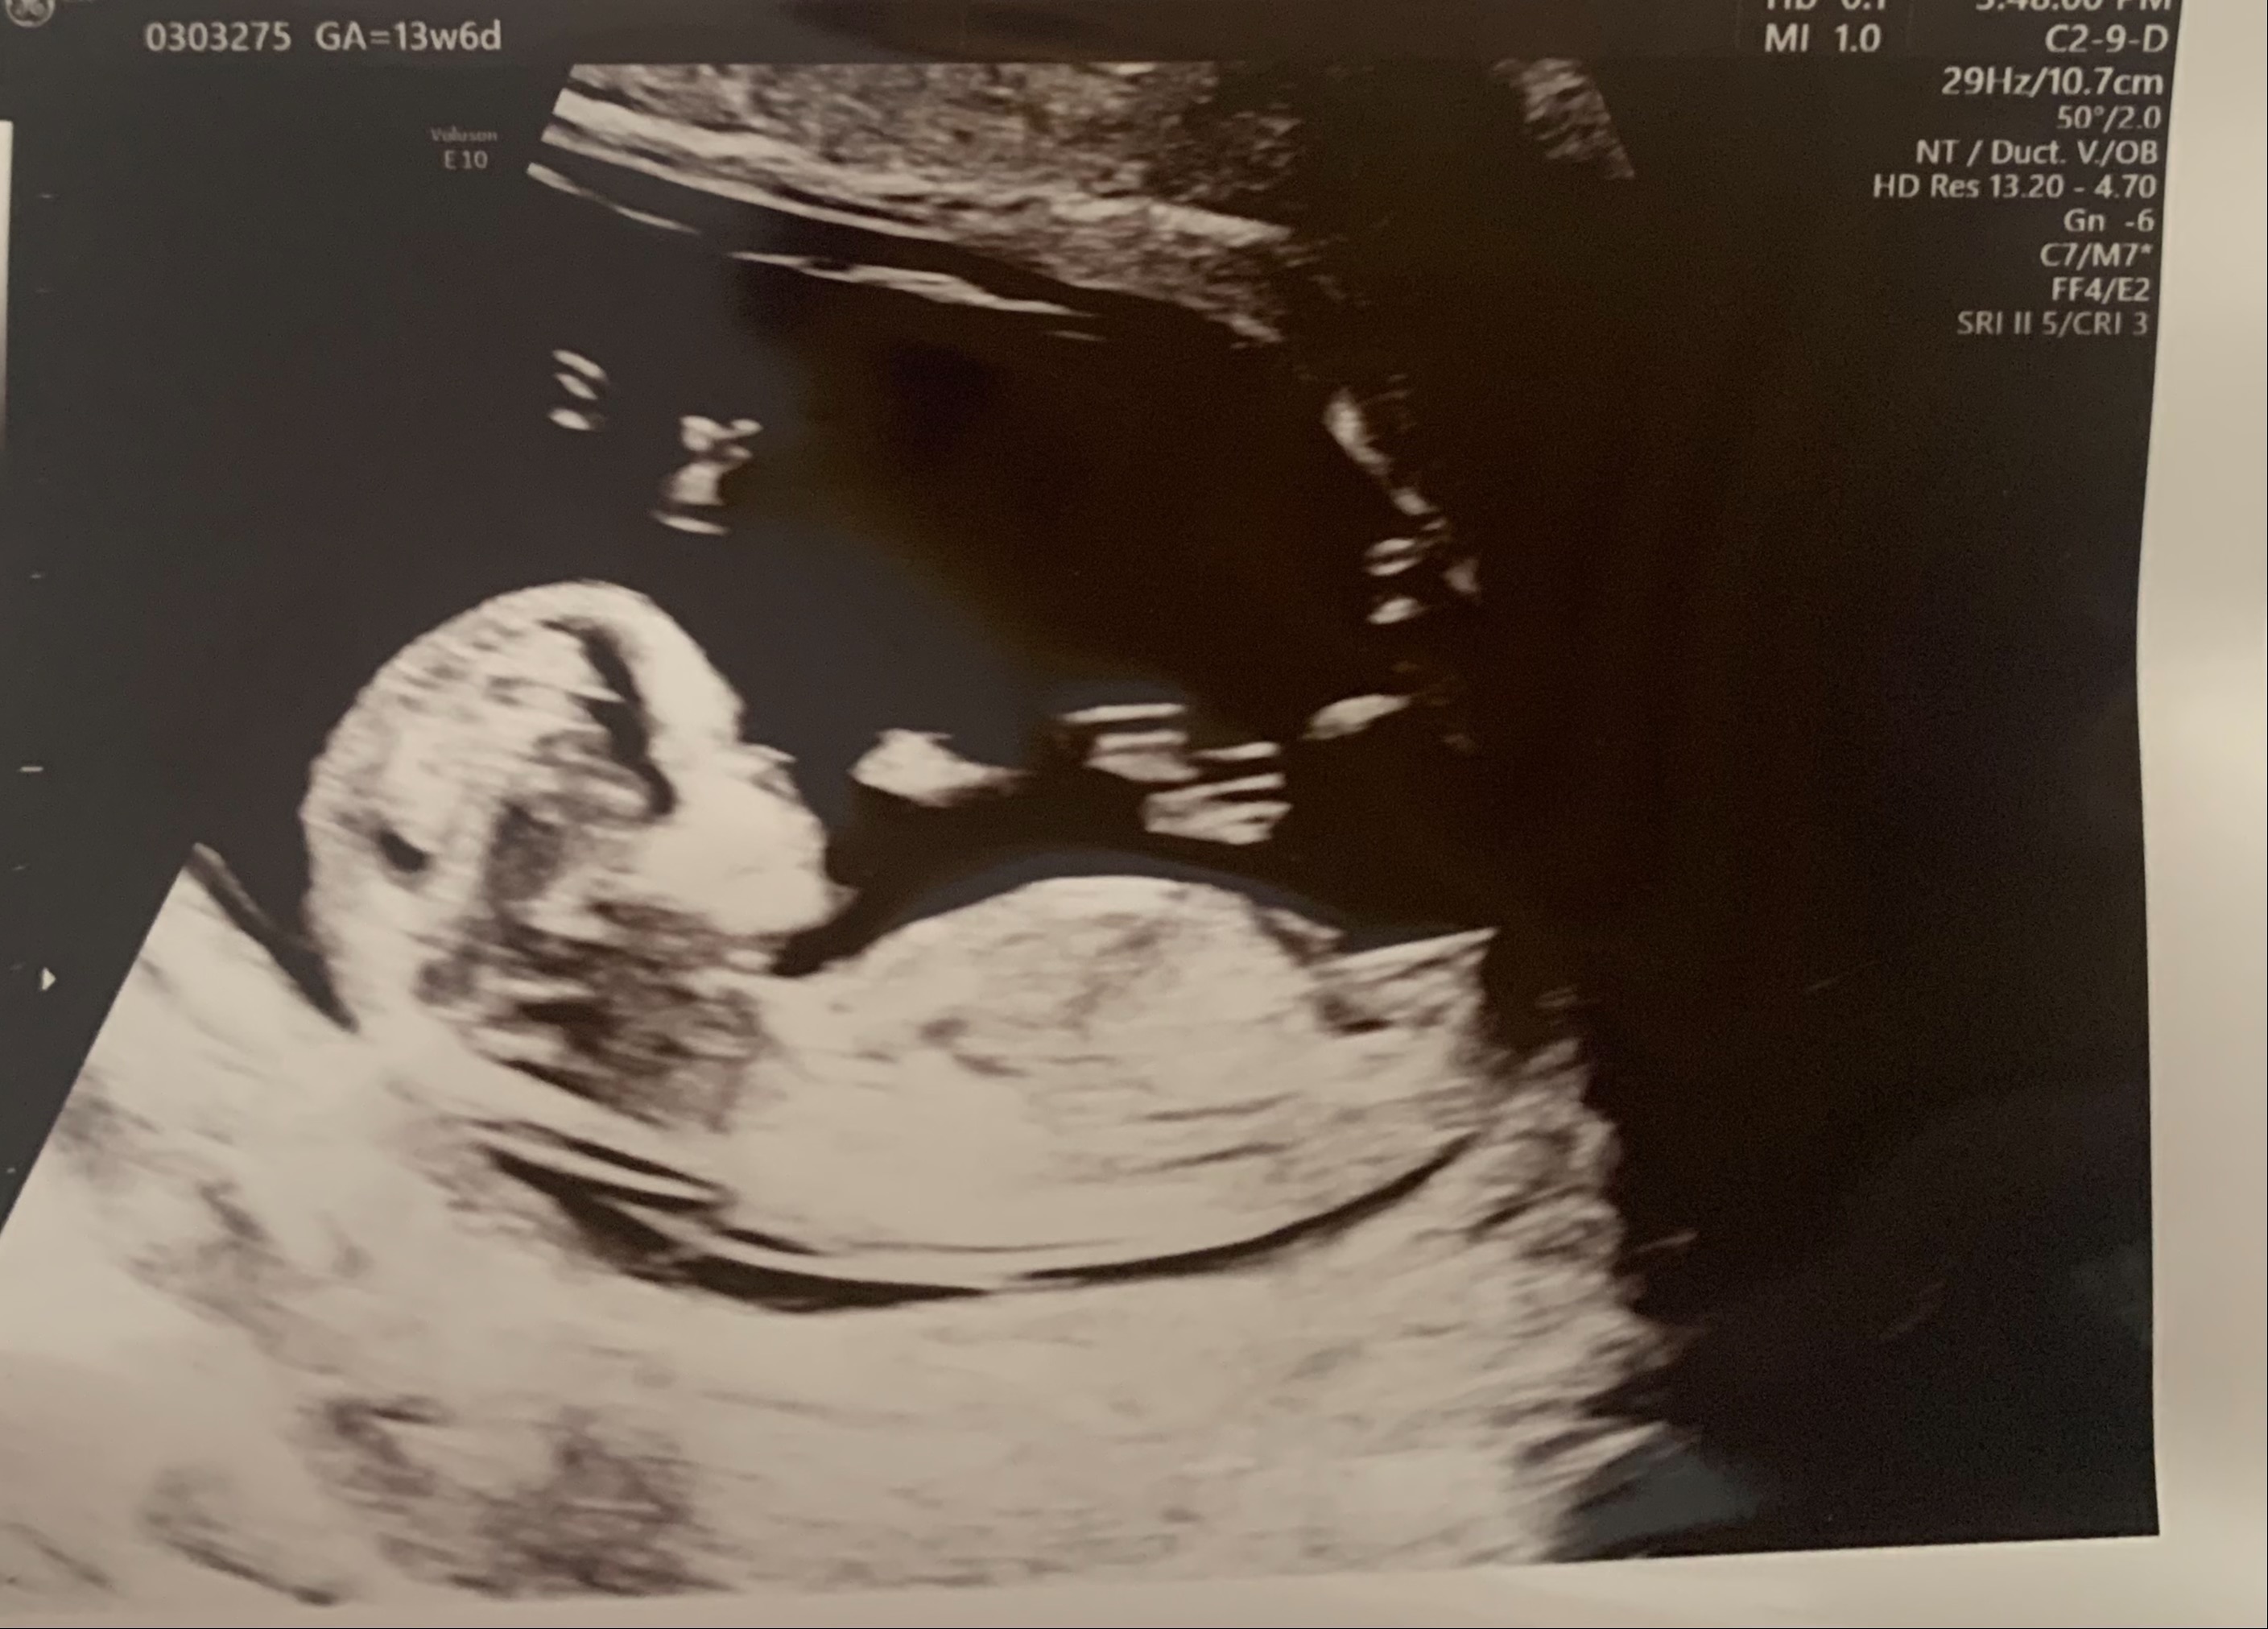

can i have a look at your ultrasound please at first

Dr Aqsa please see the ultrasound pics below

Please check now

Dr Nazish Ali please see the ultrasound reports

Doctors, please see the ultrasound pics below

dear yes because these are markers for chromosomal abnormalities usually we do NT for screening